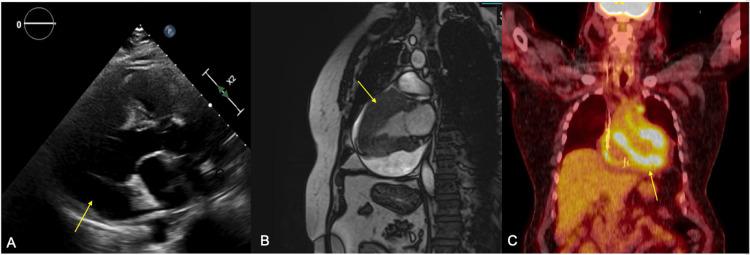

Primary cardiac lymphoma (PCL) is a rare malignant disease and its presentation varies depending on the degree of infiltration and location in the myocardium; hence its diagnosis can be challenging. We present a case of a 67-year-old otherwise healthy male who initially presented with recurrent syncope found to have a pericardial effusion and complete heart block. Paratracheal biopsy of a fluorodeoxyglucose (FDG)-avid lymph node was consistent with diffuse large B-cell lymphoma. Diagnosis is usually identified histologically, but imaging is key in guiding biopsy and monitoring disease regression. Chemotherapy is the mainstay of treatment. In this case report, we present a unique presentation of primary cardiac lymphoma presenting as complete heart block with extra-cardiac lymph node involvement and review its management.

原发性心脏淋巴瘤(PCL)是一种罕见的恶性疾病,其表现因心肌浸润程度和位置而异;因此,其诊断可能具有挑战性。我们报告一例67岁的健康男性,最初表现为反复晕厥,发现有心包积液和完全性心脏传导阻滞。对氟脱氧葡萄糖(FDG)摄取阳性的气管旁淋巴结进行活检,结果与弥漫性大B细胞淋巴瘤一致。诊断通常通过组织学确定,但影像学在指导活检和监测疾病消退方面至关重要。化疗是主要的治疗方法。在本病例报告中,我们展示了原发性心脏淋巴瘤以完全性心脏传导阻滞伴心脏外淋巴结受累的独特表现,并对其治疗进行了综述。